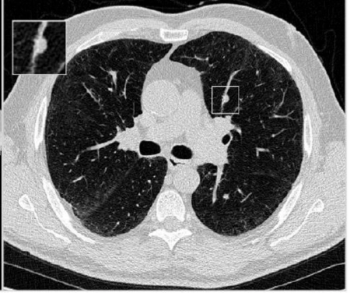

In the newly released Lung-RADS 2022 classification system for computed tomography (CT) lung cancer screening, the American College of Radiology (ACR) has noted a variety of updates including new classification criteria for atypical pulmonary cysts and airway nodules, time intervals for nodule growth and a new stepped management approach for Lung-RADS categories 3 and 4A.